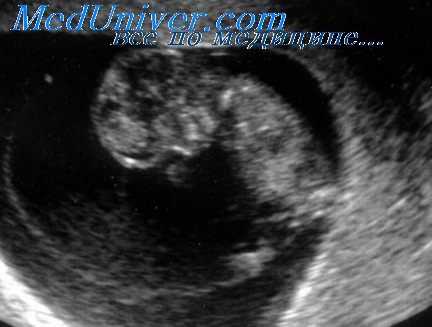

Б-я Ш. 25 лет. Эхографические признаки внематочной беременности. Эктопически расположенное плодное яйцо с живым эмбрионом (в 5–10 %) (развивающаяся беременность)

Эхокартина внематочной беременности. После оперативного лечения — небольшая гематома в дугласовом пространстве (1).